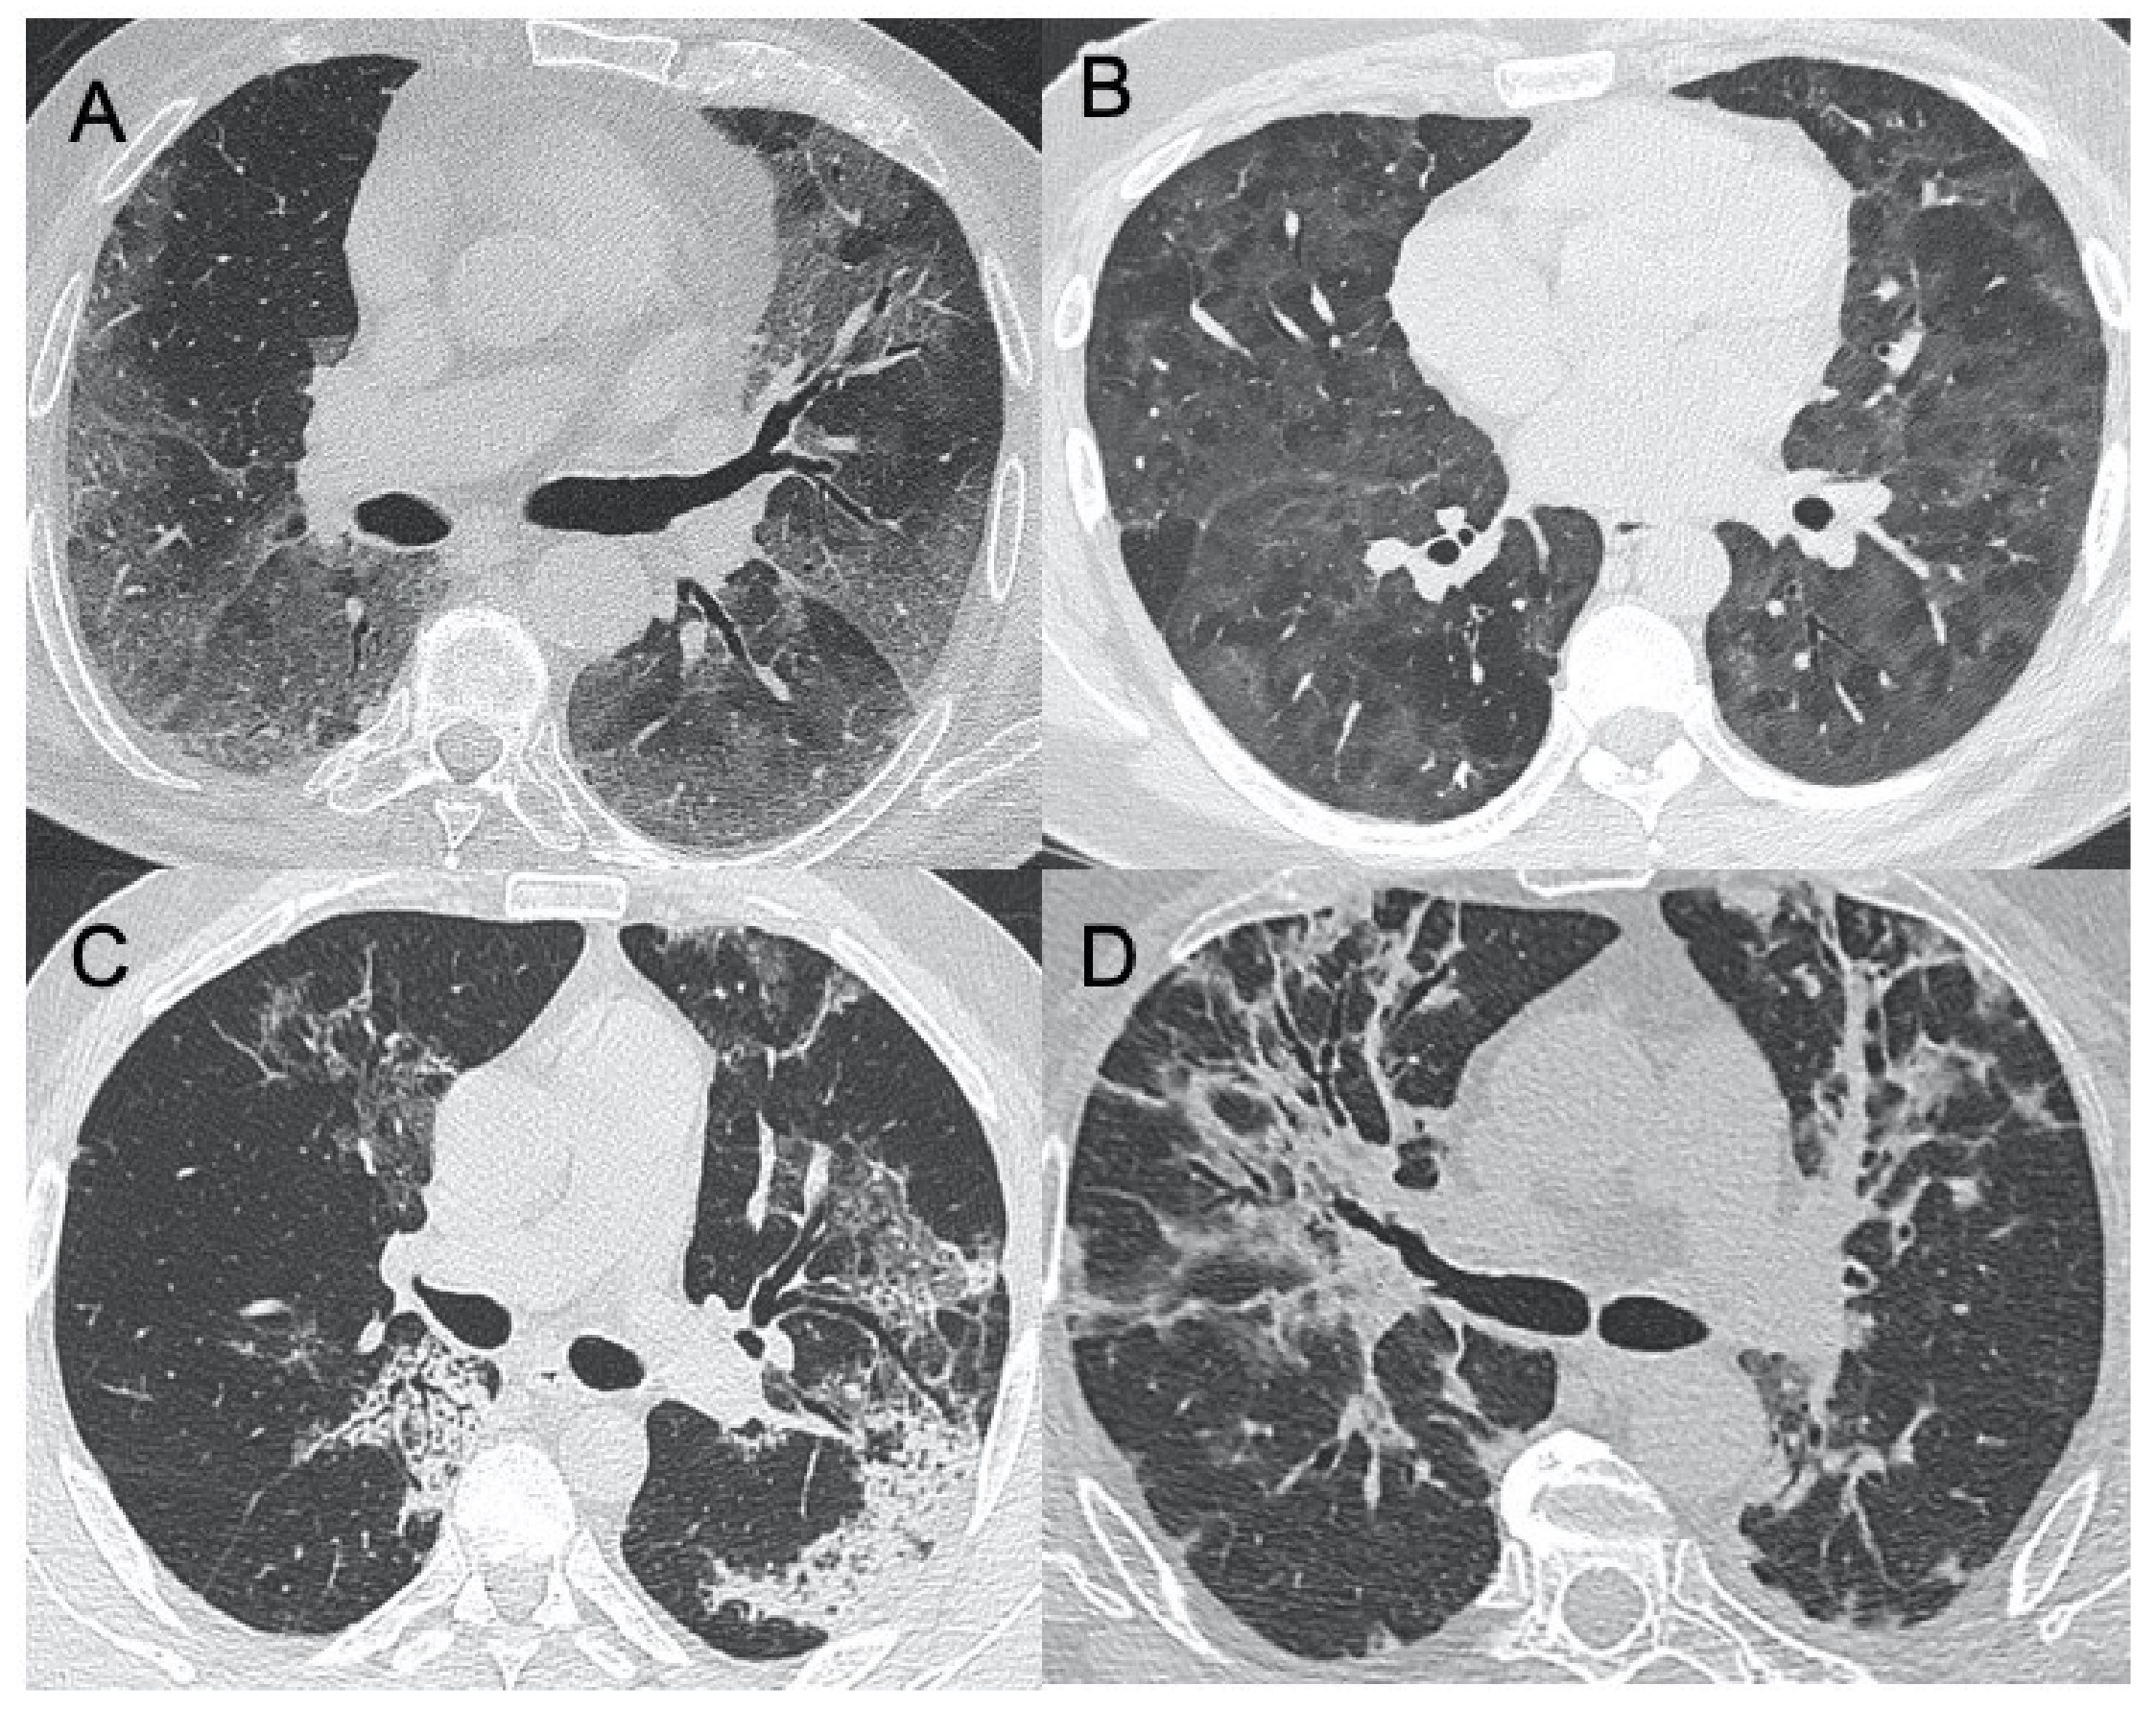

● CXR:肺胸膜下實(shí)變、磨玻璃影、結(jié)節(jié)和網(wǎng)狀結(jié)節(jié)陰影,表現(xiàn)為間質(zhì)性肺炎伴彌漫性肺泡損傷(圖1)。

● CT:早期主要為外周、雙側(cè)磨玻璃影(ground-glass opacities,GGO),伴實(shí)變、小葉間隔和小葉內(nèi)間隔增厚,形成“鋪路石征”模式。空氣支氣管征、血管擴(kuò)大、暈輪征和反暈征也有報(bào)告(圖2)。

圖1 新冠肺炎(COVID-19)的CXR。3例仰臥位CXR顯示胸膜下實(shí)變(箭頭),圖(A,B)顯示雙側(cè)受累,(C)主要為右肺受累

圖2 COVID-19的HRCT。急性期,雙肺(A)彌漫性GGO,小葉周圍型(B)。圖(C,D)顯示2例亞急性間質(zhì)性肺炎,GGO減少,存在胸膜下局灶性實(shí)變和小葉間/小葉內(nèi)間質(zhì)增厚。